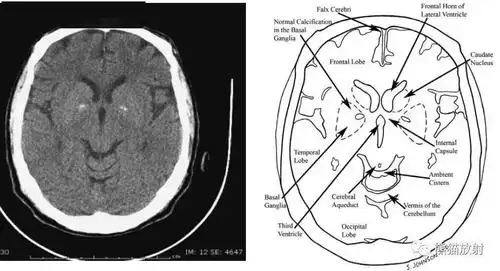

颅脑ct的正常解剖